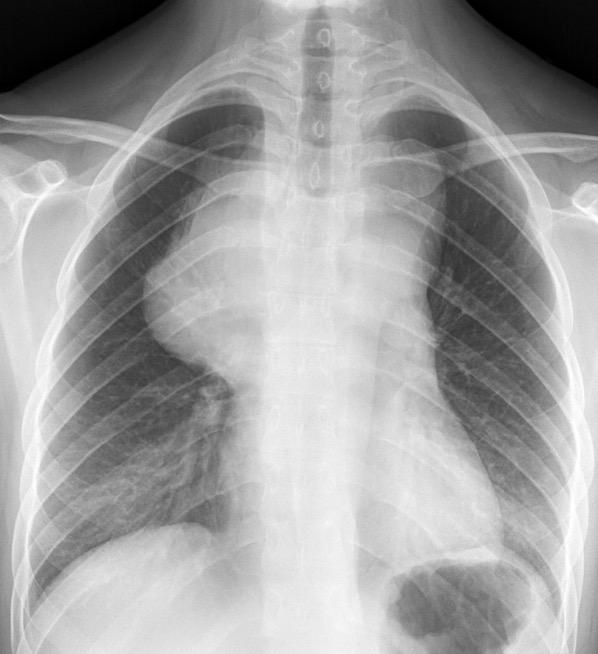

Carcinoma microcítico con síndrome de VCS

Síntomas y signos que se producen con la obstrucción total o parcial de la vena cava superior

Causas Malignas +/- 90-95%

Ca. Broncogénico (80-85%)

Linfoma No Hodgkin (15%)

Catéteres, shunts y marcapasos…23%

T. Mediastínico. Bocio

Fibrosis Idiopática

Tb, Histoplasmosis, Actinomicosis, Sarcoidosis